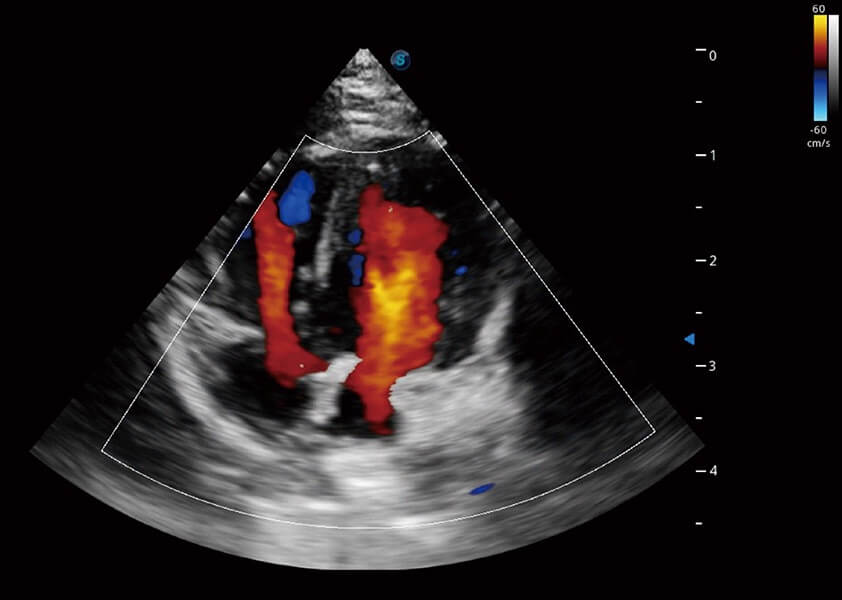

ProPet 60 作为一款高端台式动物超声设备,为动物医生的日常诊断提供了一系列贴合动物临床需求、解决临床实际问题的高级成像功能。凭借全系列高清探头,满足医生对腹部、心脏、生殖、浅表、肌骨等成像的所有需求,切实帮助您提升检查效率,提高诊断信心。

动物是人类最亲密的朋友和最值得信赖的伙伴。乐玩lewin国际也一直致力于探索动物专用的超声影像解决方案。 全新推出的ProPet系列,是乐玩lewin国际在动物超声影像智能化、专业化、精准化的一次跨越式革新。动物不能用言语来表述自己的不适,通过超声影像,ProPet系列搭建了动物医生与不同物种沟通的“桥梁”,为动物医生注入了“治愈之力”。